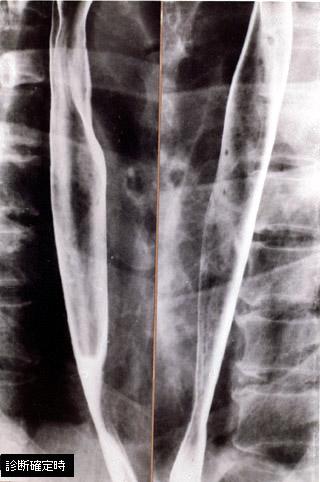

食道、胃、十二指腸に微小・微細病変を伴った小腸Crohn病の1例の食道のX線像  食道の二重造影写真です。明らかな腫瘍や大きな潰瘍の形成は認められません。ただ、粘膜面に僅かな不整が認められます。

疾患(病理主体)の分類炎症性・潰瘍性疾患/クローン病

部位(臓器別)食道/その他

検査方法X-P

病変の最大径(ミリ)1〜9